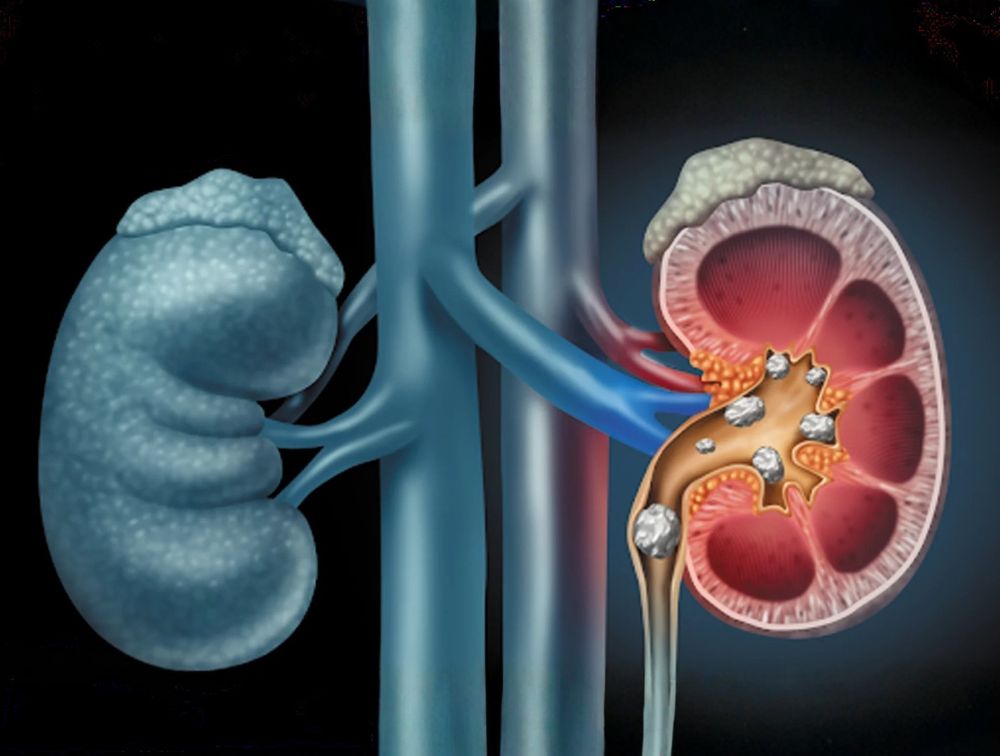

Os cálculos urinários, conhecidos como pedras nos rins, são formações sólidas que surgem quando substâncias presentes na urina se cristalizam. Eles podem variar de tamanho e estar localizados nos rins, ureteres, bexiga ou uretra.

Os sintomas mais comuns incluem dor intensa nas costas ou abdômen, dor ao urinar, sangue na urina, náuseas e vômitos. Diante desses sinais, é fundamental procurar um urologista para avaliação e definição do tratamento adequado.

O tratamento depende do tamanho e da localização do cálculo e pode envolver desde medidas clínicas, como hidratação e medicamentos, até procedimentos minimamente invasivos.

A prevenção é possível com hábitos simples, como ingerir bastante água, reduzir o consumo de sal, proteínas animais e alimentos ricos em oxalato, além de acompanhamento médico nos casos indicados.

Com o tratamento correto e mudanças no estilo de vida, é possível resolver o problema e reduzir o risco de novos cálculos.

A cirurgia para cálculos urinários evoluiu significativamente. Hoje, a maioria dos procedimentos é feita sem cortes, por via endoscópica, utilizando aparelhos finos introduzidos pela uretra.

Por meio do uso de laser, o cálculo é fragmentado em partículas muito pequenas, que podem ser removidas ou eliminadas naturalmente.

Em casos específicos, como cálculos maiores localizados nos rins, pode ser necessário um pequeno acesso pela pele, permitindo a retirada completa da pedra.

Essas técnicas oferecem alta eficácia, rápida recuperação e, em muitos casos, possibilitam alta hospitalar no mesmo dia.

O cálculo coraliforme é um tipo mais complexo de cálculo, que ocupa parte ou todo o sistema coletor do rim, podendo estar associado a infecções urinárias de repetição e perda da função renal.

O tratamento tem como objetivo a remoção completa do cálculo e a prevenção de novos episódios. A principal abordagem é cirúrgica, utilizando técnicas endoscópicas avançadas, como a nefrolitotripsia percutânea, com pequenos acessos e aparelhos miniaturizados.

Em alguns casos, a combinação de acessos permite alcançar todas as áreas do rim, aumentando a eficácia do tratamento. A recuperação costuma ser rápida, com menos dor e bons resultados funcionais.

Após o tratamento, o acompanhamento médico e as medidas preventivas são essenciais para preservar a saúde renal e evitar recidivas.